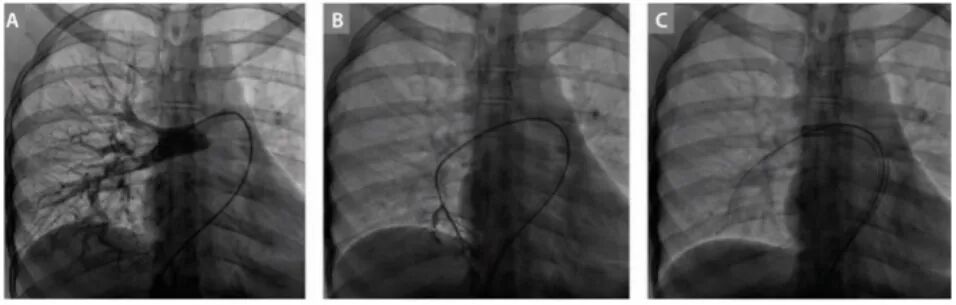

1、止血(不漏血)

大动脉(胸主/腹主),结构心脏病(主瓣,二尖瓣)等手术,鞘的漏血是临床痛点。气囊结构完美解决,减少漏血风险。

血管鞘组是什么器械百科丨Corpassing泊淮™ 导管鞘组_https://www.jmylbn.com_新闻资讯_第10张

气囊设计